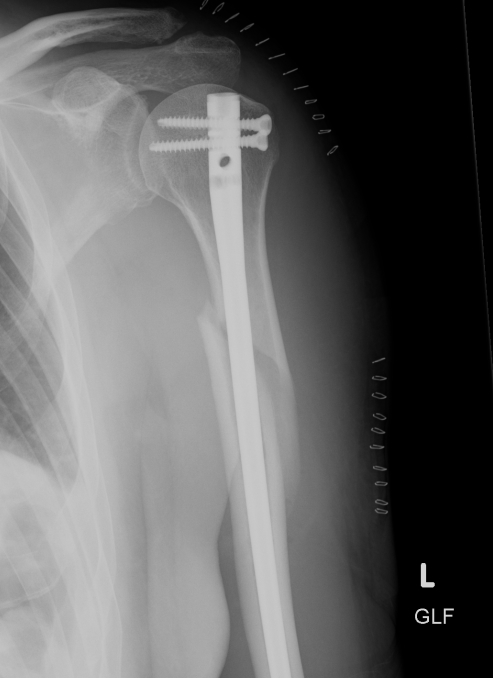

Prox humerus 1Prox humerus 2Prox humerus ORIFProximal humerus ORIF

Proximal third humerus ORIF of nonunion